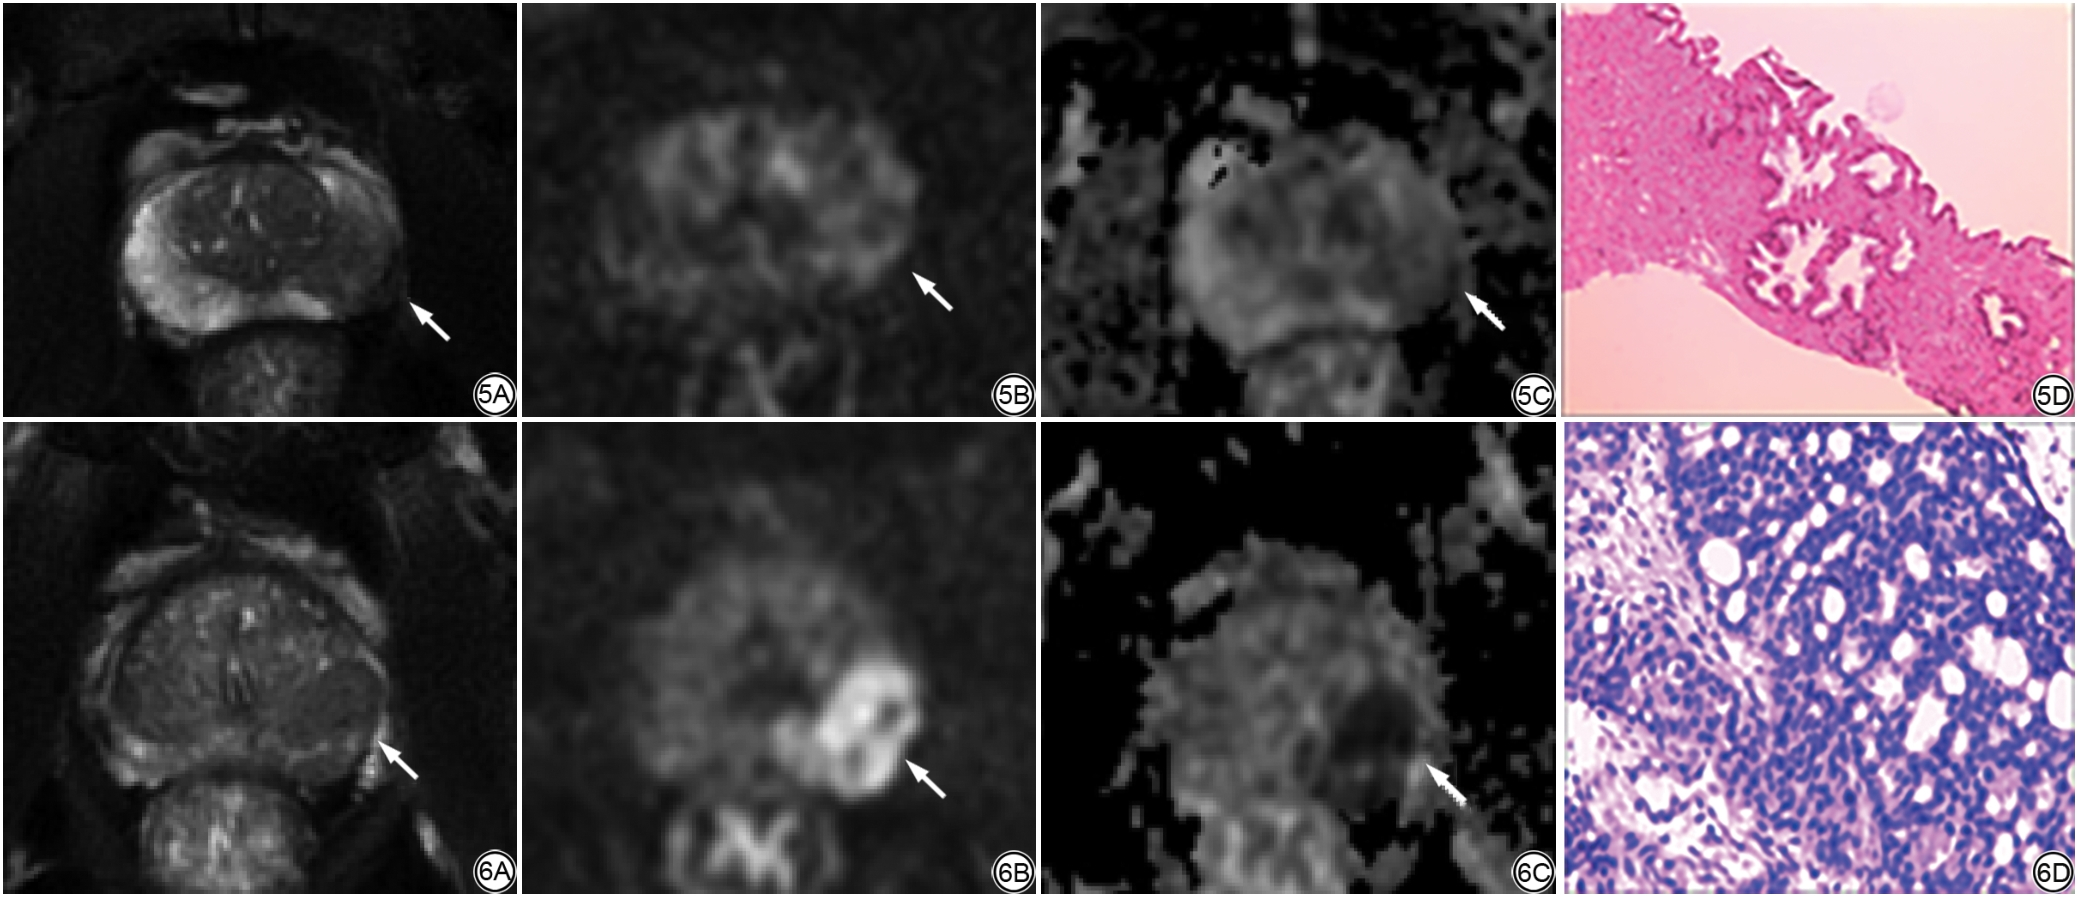

将PI-RADS v2.1的评分分级与PSAD值的风险分层进行组合。对于tPSA 4~20 ng/mL的患者,当PI-RADS v2.1评分≤2,无论PSAD值如何,csPCa检出率均小于5%,均可避免不必要的活检。当PI-RADS v2.1为3分且联合PSAD值的风险分层时,csPCa检出率分别为11.8%、9.4%、25.0%。当PI-RADS v2.1为4~5分且联合PSAD值的风险分层时,csPCa检出率为分别为28.0%、46.5%、81.3%(表5)。典型病例见图5图6

图5  男,58岁,PV为45.38 mL,tPSA为7.66 ng/mL,PSAD为0.17 ng/mL2。5A:T2WI轴位,左侧外周带示斑片状中等低信号灶(箭)、边界欠清;5B:DWI(b值=1000 s/mm2)轴位,病灶呈斑片状稍高信号(箭);5C:轴位ADC,病灶呈稍低信号(箭),PI-RADS v2.1评分为3分;5D:病理结果(HE ×100)为前列腺增生伴前列腺炎。

图6  男,58岁,PV为42.83 mL,tPSA为13.1 ng/mL,PSAD为0.31 ng/mL2。6A:轴位T2WI示左侧外周带低信号灶(箭)、边界清楚,直径约1.7 cm;6B:DWI(b值=1000 s/mm2)轴位,病灶明显高信号(箭);6C:ADC轴位,病灶明显低信号(箭),PI-RADS v2.1评分为5分;6D:病理结果(HE ×100)为前列腺癌(Gleason评分3+4=7分,WHO/ISUP分级分组为2组)。PV:前列腺体积;tPSA:总前列腺特异性抗原;PSAD:前列腺特异性抗原密度;DWI:扩散加权成像;ADC:表观扩散系数;PI-RADS v2.1:前列腺影像报告和数据系统2.1版;WHO:世界卫生组织;ISUP:国际泌尿病理学会。

Fig. 5  Male, 58 years old, PV is 45.38 mL, tPSA is 7.66 ng/mL, PSAD is 0.17 ng/mL2. 5A: T2WI axial with unclear boundary and medium-low signal focus (arrow) at the periphery of the left peripheral zone; 5B: DWI (b value = 1000 s/mm2) axial, the lesion shows slightly hypersignal (arrow); 5C: ADC axial, the lesion is slightly low signal (arrow), the score of PI-RADS v2.1 is 3 points; 5D: Pathological result (HE staining × 100) shows prostatic hyperplasia with prostatitis.

Fig. 6  Male, 58 years old, PV is 42.83 mL, tPSA is 13.1 ng/mL, PSAD is 0.31 ng/mL2. 6A: T2WI axial with clear low-signal focus (arrow) at the periphery of the left peripheral zone, and the maximum diameter is approximately 1.7 cm; 6B: DWI (b value = 1000 s/mm2) axial, the lesion shows obvious hypersignal (arrow); 6C: ADC axial, the lesion is significantly low signal (arrow), the score of PI-RADS v2.1 is 5 points; 6D: Pathological result (HE staining × 100) shows prostate cancer (Gleason score 3+4=7, WHO/ISUP graded into 2 group). PV: prostate volume; tPSA: total prostate specific antigen; PSAD: prostate specific antigen density; DWI: diffusion-weighted imaging; ADC: apparent diffusion coefficient; PI-RADS v2.1: prostate imaging report and data system version 2.1; WHO: World Health Organization; ISUP: International Society of Urological Pathology.